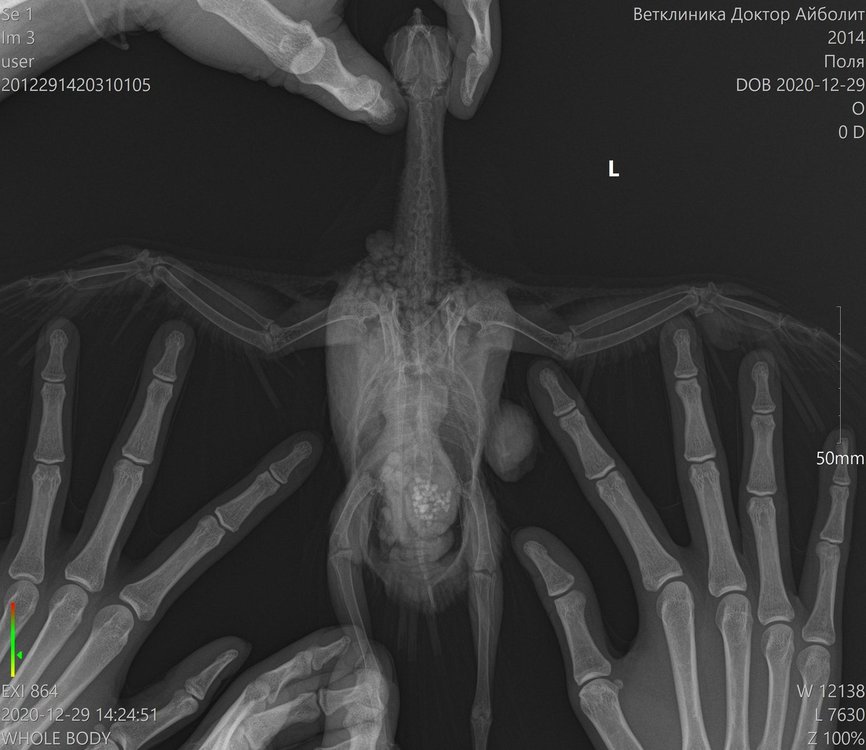

Lia V Опубликовано 30 декабря, 2020 Автор #25 Опубликовано 30 декабря, 2020 Добрый вечер, как обещала, рассказываю о результатах похода к хирургу. Вчера сделали операцию моему красавцу. Он, мягко говоря был сильно удивлен, сказал, что ранее такого не встречал. Приложу фото, которое он сделал во время операции. Этих шишек было 2, размеры и скорость роста шокируют (((((((((( одну хорошо видно на рентгене, вторая была на крыле (на плече, она была меньше, скрыта в перьях и не так заметна, на фото именно она). Природа этих наростов не ясна((((( Гистология будет готова только через 21 день. Назначили пить амоксиклав, флуконазол, гепатовет, кальция глюконат, транексам, ветом. Завтра записалась на контрольный повторный прием к орнитологу. Попрошу ее дотошно его с ног до ушей осмотреть (у меня это получается плохо, он вертится, я все время боюсь, что швы разойдутся и не рискую его сильно крутить. У врача, естественно, это получается ловко и умело). По цене операция + 2 проекции рентгенографии и гистология вышли в 7.300 руб. Сидит мой Поля с собранным крылом, в воротнике, летать не пускаю, гуляет только по клетке. Скучно ему. От избытка энергии чистится как дурной (ему больше реально и делать нечего), воротник спасает лишь частично, я все переживаю как бы не расковырял раны. Честно говоря, у меня паника и ощущение полой неопределенности. Спасибо врачам огромное, но ситуация все равно пока не ясная совершенно. Встречалась ли Вам такая ситуация??? Что это может быть???

Zosia Опубликовано 30 декабря, 2020 #26 Опубликовано 30 декабря, 2020 Меланома или меланоцитома. Встречались, конечно... Кроме всего прочего у птицы гипертрофия сердечной мышцы, дилатированное сердце. Есть так же некие объекты по верхней границы печени (в ВД проекции) и справа (для смотрящего на снимок- слева) https://public.fotki.com/Shemlik/cancer/operacia001.html https://public.fotki.com/Shemlik/cancer/55.html https://public.fotki.com/Shemlik/cancer/59.html#media https://public.fotki.com/Shemlik/cancer/05-09-20-002.html https://public.fotki.com/Shemlik/cancer/05-09-20-001.html#media